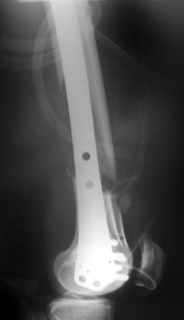

This is what we have done... As generally true for LISS look at the bone not the hardware.

There are two more srews above. The one not completely in got damaged head.

Look what we would have done.